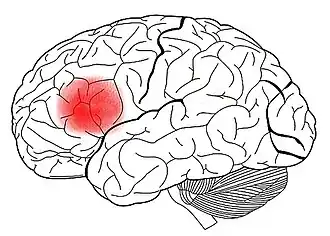

Cerebro y lenguaje

La gran mayoría de los procesos que permiten el lenguaje se llevan a cabo en diferentes áreas de asociación. Existen dos áreas bien identificadas, las cuales son consideradas vitales para la comunicación humana: el área de Wernicke y el área de Broca. Estas áreas están localizadas en el hemisferio dominante (que es el izquierdo en el 97 % de las personas) y son consideradas las más importantes en cuanto a procesamiento de lenguaje. Esta es la razón por la cual el lenguaje es considerado como una función lateralizada.[34] Sin embargo, el hemisferio no dominante también participa en el lenguaje, aunque existen cuestionamientos acerca del nivel de participación de las áreas localizadas en dicho hemisferio.[35]

El área de Wernicke, se conoce así en honor al neurólogo que la describió por primera vez. Está especialmente desarrollada en el hemisferio dominante para el lenguaje, que, generalmente suele ser el lado izquierdo. El desarrollo de esta área permite alcanzar niveles altos de comprensión y procesar la mayor parte de las funciones intelectuales del cerebro. Se encarga de la decodificación de lo oído y de la preparación de posibles respuestas. Es importante para la comprensión de palabras y en los discursos significativos.

Da paso después al área de Broca, también conocida como el área motora de las palabras, que se conecta con el área de Wernicke mediante el fascículo longitudinal superior. Se ubica en la corteza prefrontal, en la parte anterior de la porción inferior de la corteza motora primaria, cercana a la fisura lateral (FL). En la mayoría de los casos, es dominante en el lado izquierdo del cerebro. Su función es permitir la realización de los patrones motores para la expresión de las palabras, articulando el lenguaje hablado y también el escrito. Es la responsable de la formación de las palabras en la que se activa el accionamiento de los músculos fonadores, es decir laríngeos, respiratorios y de la boca, para asegurar la producción de sonidos articulados, lo que tiene lugar en el área motora primaria, de donde parten las órdenes a los músculos fonadores. Además se conecta con el área motora suplementaria, que tiene relación con la iniciación del habla.

Las diferencias funcionales entre hemisferios son mínimas y solo en algunas pocas áreas se han podido encontrar diferencias en cuanto a funcionamiento, existiendo excepciones en personas que no se observaron diferencias. Las áreas actualmente más conocidas especializadas en el lenguaje son la de Broca y la de Wernicke, aunque al hacer un proceso lingüístico es probable que todo el cerebro esté involucrado —casi indudablemente las áreas de la memoria participan en el proceso del lenguaje—. Las áreas de Broca y de Wernicke se encuentran, en la mayoría de los individuos, en el hemisferio izquierdo. Por su parte, las áreas más involucradas en la lógica y actividades intelectuales se ubican principalmente en la corteza prefrontal, teniendo quizás las áreas temporales izquierdas gran importancia para procesos de análisis y síntesis como los que permiten hacer cálculos (matemáticos); estas áreas dotan al individuo de mayor capacidad de adaptación al medio, pero con procesos de aprendizaje mucho más dilatados, y como tal más dependientes de sus progenitores durante la etapa de cría.